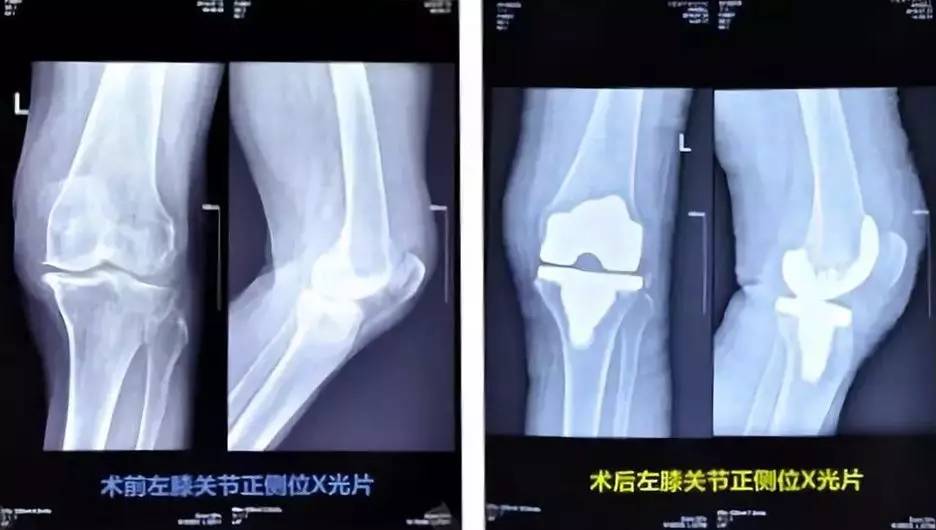

今年7月,李老太来到康华医院骨外科就诊,专家诊断她的左侧膝关节退行性病变,关节间隙狭窄,软骨下硬化明显,左膝关节骨性病变严重。医院骨外科团队成功地为她实施了人工全膝关节置换术,术后第三天,她就下床开始按医生治疗方案进行康复训练,在医护人员的搀扶下训练行走。目前李老太已康复。

将关节切开,去掉有病变的关节软骨及其下方部分骨质,切除骨刺及增生的滑膜组织,松解挛缩的关节囊,然后将预制好的金属或高分子材料制成的关节假体,通过骨水泥粘着,放置在截骨表面,最后缝合关节。